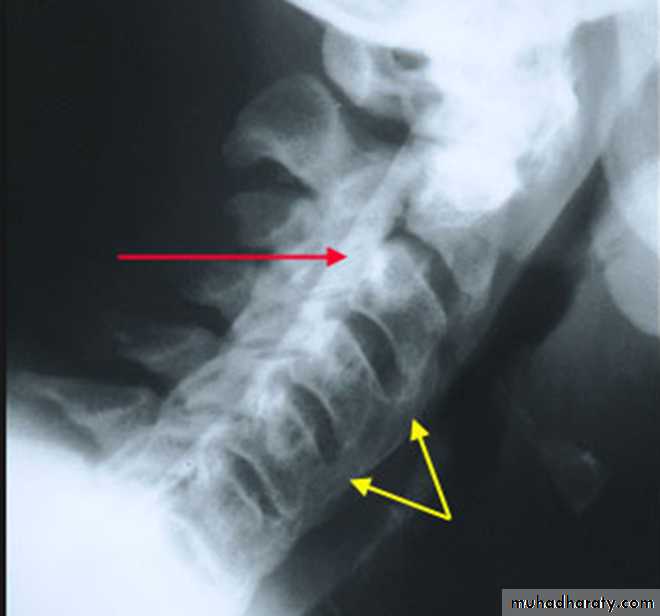

In the Spine :

* Lower cervical and low lumbar spine are most comonly affected.* Osteophytes may encroach on neural foramina (best seen on oblique views).

*Vacuum phenomenon: gas (N2),is pathognomonic of the degenerative process.

* OA of the spine occurs in the apophyseal joints .

* Degenerative spondylolisthesis (pseudospondylolithesis)

Lumbar spondylosis. There is distal narrowing and a vacuum

phenomenon is present in the degenerative discs. Marginal osteophytes arepresent. Inferiorly the facet joints show features of degeneration and, with the increase in lordosis, the spinous processes are in contact

Cervical spondylosis